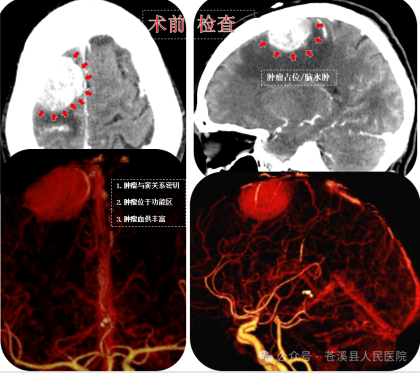

▲术前CT与CTA检查肿瘤血供极其丰富。

为最大程度的保护重要的神经滋养动脉、上矢状窦及脑组织表面的回流静脉,神经外科医疗团队结合术前检查,多次组织全科进行术前方案讨论,最终决定,在不造成神经功能影响的前提下全切肿瘤组织。